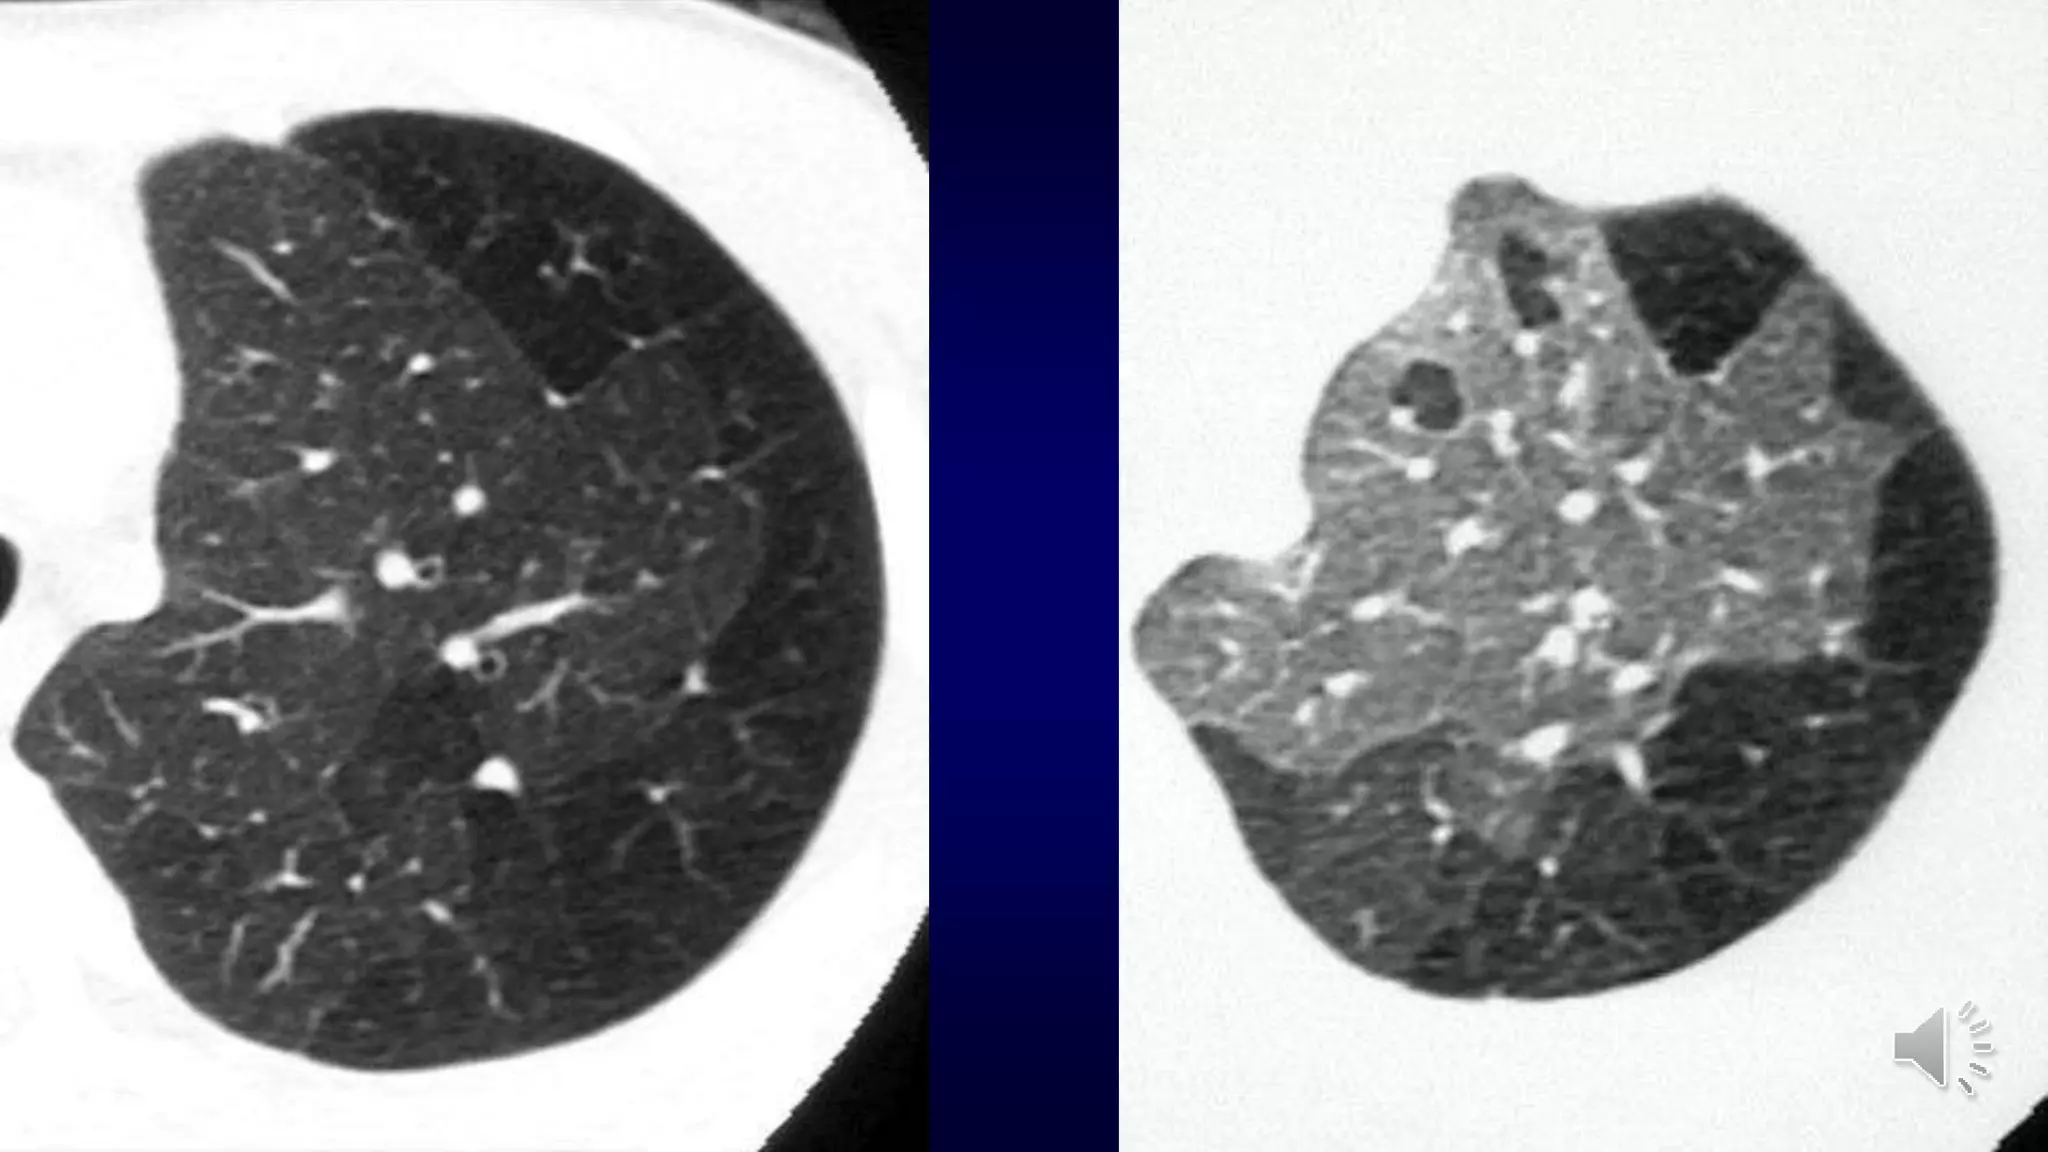

Initial CT-findings

Initial CT-findings in COVID-19 cases include bilateral,

multilobar ground glass opacification (GGO) with a peripheral

or posterior distribution, mainly in the lower lobes and less

frequently in the middle lobe .

Consolidation superimposed on GGO as the initial imaging

presentation is found in a smaller number of cases, mainly in

the elderly population.

Septal thickening, bronchiectasis, pleural thickening, and

subpleural involvement are some of the less common

findings, mainly in the later stages of the disease.